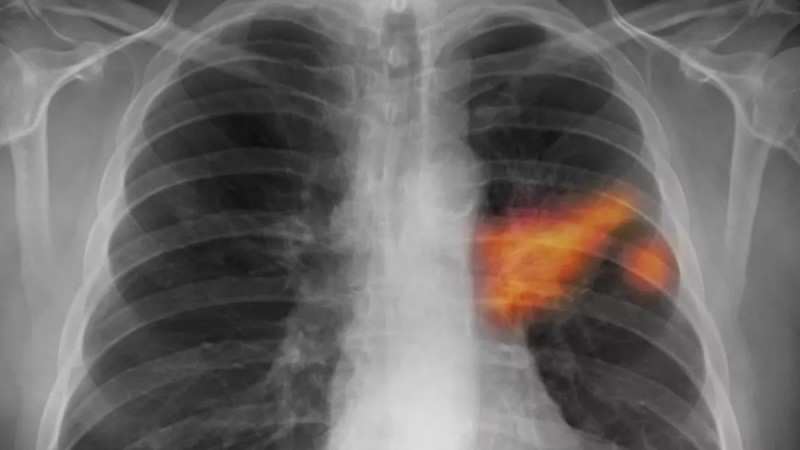

V České republice každoročně diagnostikují přibližně 6 500 případů rakoviny plic, která v časných stádiích neprojevuje žádné příznaky, což zvyšuje úmrtnost, ale díky novému screeningovému programu zaměřenému na ohrožené skupiny, zejména kuřáky ve věku 55 až 74 let, je možné rakovinu včas odhalit a tím výrazně zlepšit šance na úspěšnou léčbu. #rakovinaplic #prevence #screening

V počátečních stádiích nemá rakovina plic žádné příznaky. Každý Čech se může nechat otestovat

Rok co rok je rakovina plic odhalena u více než 6500 pacientů, přičemž pouze u jednoho z deseti je diagnóza stanovena včasné léčitelném stádiu, přičemž preventivní screening pomůže každému druhému vyšetřenému, avšak polovina oslovených na něj nedochází a praktický lékaři tento vyšetřovací program nabízejí jen polovině svých pacientů. #rakovinaplic #screening #prevencetumoru

Jeden z deseti nádorů plic zachytí lékaři včas, při preventivním vyšetření pět

že většina z nich ji podchytí až v pokročilém stádiu, ale díky modernímu on-line screeningu máme nyní šanci odhalit rakovinu plic včas a zachránit životy! #Zdraví #Screening #RakovinaPlic